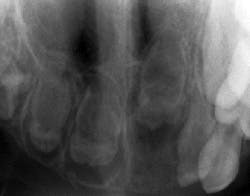

Because of the limited areas affected, diagnosis is usually made with regard to RO by clinical and radiographic analysis. Radiographically, the teeth are seen as poorly developed with very little dentin or enamel showing calcification, thereby presenting with a less radiopaque appearance than a normally developed tooth. Because of this poor development and the lack of calcification, they have been termed “ghost teeth” with only a shadow of a tooth present (see Figure 2).